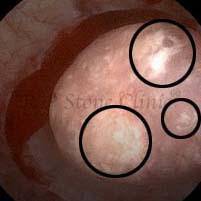

These images are taken as snap shots from the video recording of RIRS Surgery done at our hospital. These are Randall’s Plaques seen with Digital FLEX XC & Digital FLEX XC S. The cream or whitish patches are seen on the tips of RENAL PAPILLAE as seen in images below.

The Below Images Show Small Stones attached to the Renal Papillae.